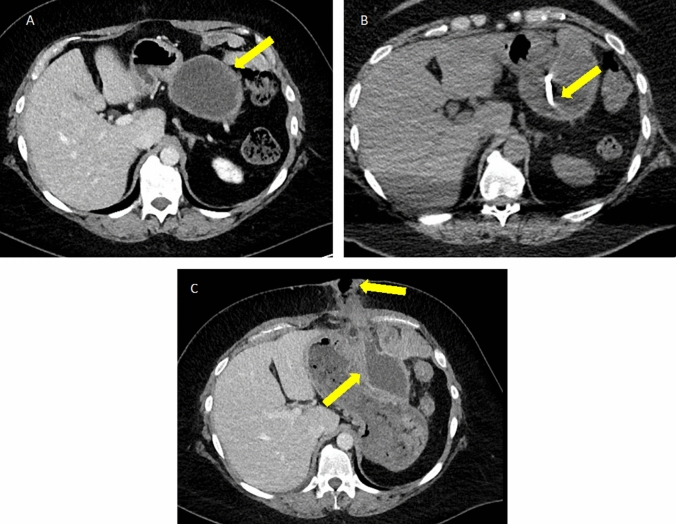

Fig. 11.

Peripancreatic and pancreatic collections in necrotizing pancreatitis. A Axial IV contrast-enhanced CT in a patient with acute NP and ANCs involving the pancreatic parenchyma (arrowhead) and the peripancreatic tissues (arrow). B Axial IV contrast-enhanced CT in a patient with NP and a large area of WON occupying the pancreatic body and tail with an enhancing capsule (arrows). Note the heterogeneous appearance of the collections in NP which contains fluid density intermixed with fat density